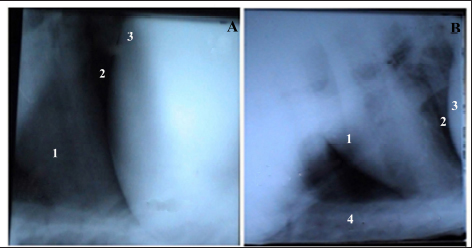

Radiography showed that the reticulum in healthy buffaloes was radio-opaque and free from any metal bodies. The reticulum and heart were radio-opaque structures, and the diaphragm was visualized as a prominent black line separating them. Adhesions between the heart and diaphragm or between the reticulum and diaphragm were not seen. The heart, as was a radio-opaque structure, had clear borders and a regular size and shape (Fig. 1a and b).

Fig. 1. Lateral radiographic view of the cranial abdomen (a) and the thorax (b) of a 3-year non-pregnant female buffalo showed the normal radiographic appearance of the reticulum, heart, and diaphragm. 1; Heart. 2; Diaphragm. 3; Reticulum. 4; Sternum.